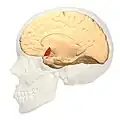

Animation.

Medial view.

Medial view.